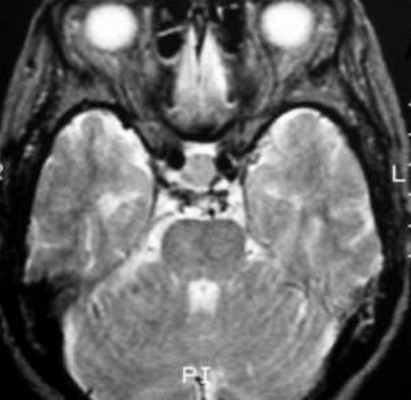

![f2]()

Т2-взвешенное аксиальное изображение (тот же пациент, что и на предыдущем изображении).